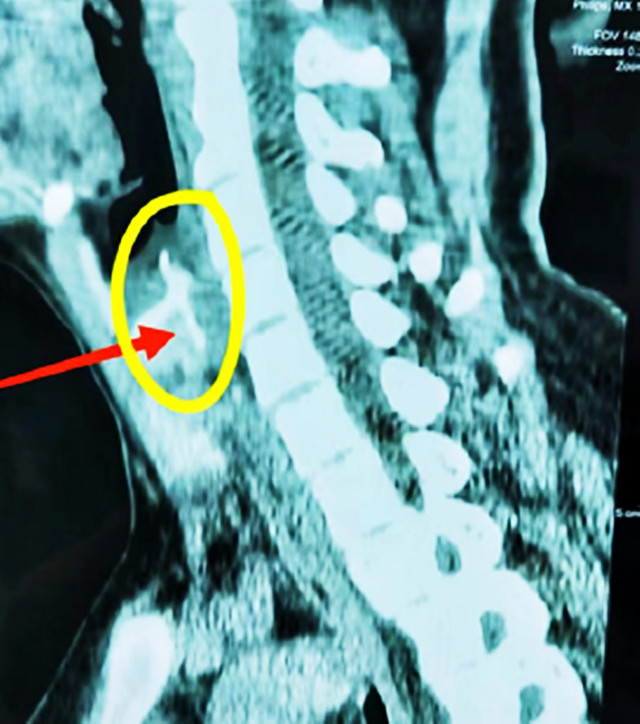

原因:鱼刺可能刺入食道壁、主动脉等深部组织,或导致食道穿孔。

表现:吞咽时疼痛剧烈,甚至无法吞咽唾液,疼痛放射至背部或胸部,静止时也持续疼痛。

提示:若胸痛伴随心慌、冷汗,需警惕鱼刺损伤大血管(如主动脉),可能引发大出血。